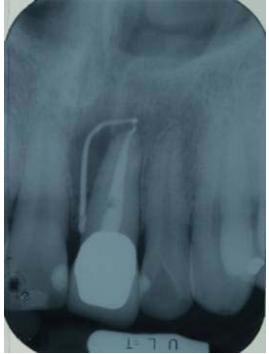

26.承上題,下圖為這顆第一小臼齒完成根管充填後所拍攝的X光片。請問依據Weine的分類定義, 這顆牙齒的根管形態是屬於那一型,而發生根管過度充填(overfilling)是那一個根管?

(A)第二型根管形態,頰側根管 (B)第二型根管形態,顎側根管 (C)第三型根管形態,頰側根管 (D)第三型根管形態,顎側根管